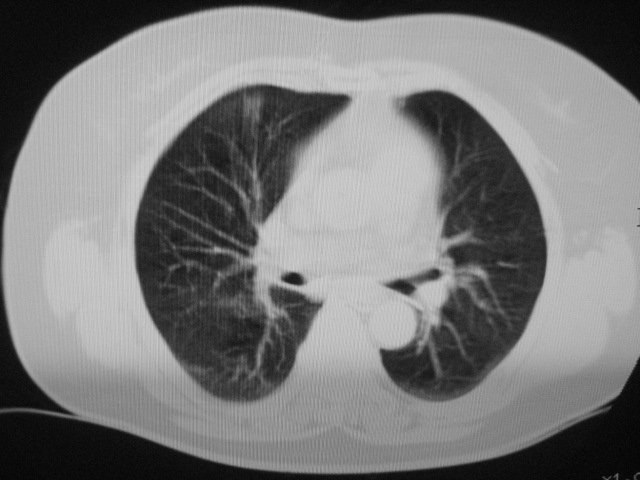

以下是引用清清楚楚在2007-8-28 7:13:00的发言:[br]右肺下叶可见斑片状高密度影,边缘模糊;右肺中叶内侧段及左肺舌段亦可见小斑片状模糊影。[br]考虑双肺感染,建议抗炎治疗后复查。

以下是引用天南地北在2007-8-27 23:49:00的发言:[br]右肺下叶可见斑片状高密度影,边缘模糊;右肺中叶内侧段及左肺舌段亦可见小斑片状模糊影。[br]考虑双肺感染,建议积极抗炎治疗后复查。

以下是引用天南地北在2007-8-27 23:49:00的发言:[br]右肺下叶可见斑片状高密度影,边缘模糊;右肺中叶内侧段及左肺舌段亦可见小斑片状模糊影。[br]考虑双肺感染,建议抗炎治疗后复查。

以下是引用难听在2007-8-28 13:17:00的发言:[br]右肺下叶背段支气管狭窄,是否可以考虑新生物伴阻塞性肺炎.请大家帮帮忙,这个病人是卫生局长的丈母娘.惹不起啊.